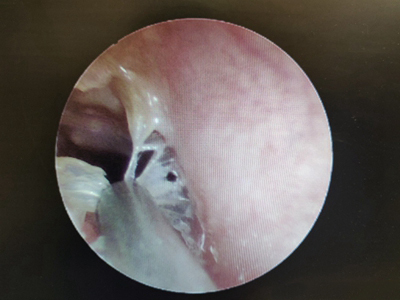

外耳道

脱屑 · 化脓

霉菌性外耳道炎耳朵里有脓性分泌物图

霉菌性外耳道炎患者的外耳道处有大量黄白色脓液性分泌物,团块状附着于外耳道壁上,边缘有碎纸样白色鳞屑,耳朵内部黏液呈灰黑色,伴瘙痒感。